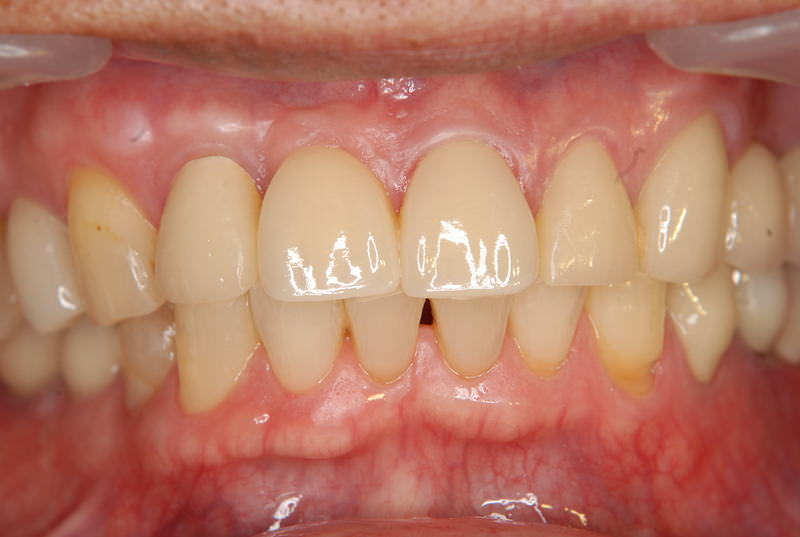

症例470歳 男性 主訴 前歯部がグラグラし、噛みにくい

治療前

治療後(3年経過)

※説明

主訴 前歯部ブリッジの動揺の為来院。歯ぎしり、喰いしばりによる力の影響である為、つなげるブリッジではなく、インプラントを選択。インプラント埋入と同時に即時荷重非接触型の仮歯を装着。

約4ヶ月後の免荷期間を経て、ジルコニアを装着。

リスクとしては、外科的侵襲がある。デメリットは、保険外診療の為、経済的負担がある。

費用 53万(税込)(オペ・仮歯・最終補綴物まで含む)